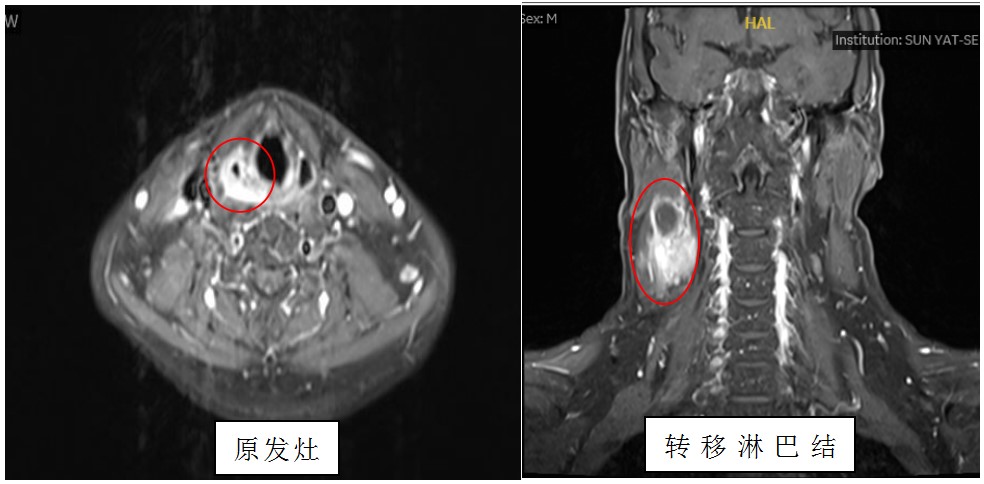

入院后经过详细检查,黄晓明教授团队发现沈先生的肿瘤位于右侧梨状窝,上下径达到3厘米,侵犯周围组织并且伴有右侧颈部淋巴结转移,诊断为下咽癌,临床分期T2N3M0,为晚期病例。

(图说:术前MR显示,患者的右侧梨状窝癌伴右侧颈部淋巴结转移)